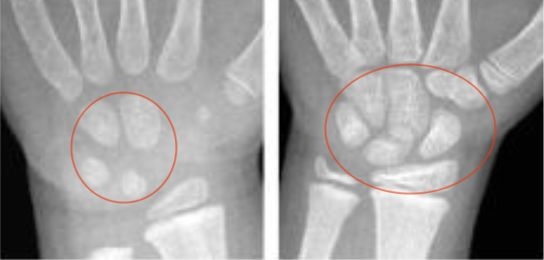

二是依据腕骨的多少、密度来判断。腕骨越少,生长空间越大,骨龄越小。

△骨龄越小,腕骨数量、密度越小